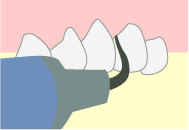

歯石除去

歯周病の原因になる細菌が含まれた歯石は、硬くなって歯に付着しているため、普段の歯磨きでは落とすことができません。そのため、定期的に歯科医院で専用の器具を用いた歯石除去を受けることがとても大切です。

スケーリング/SRP

歯と歯ぐきの間に汚れがたまることが原因で炎症が起こると歯周ポケットはどんどん深くなっていきます。

麻酔をして専用の器具を用いて歯の根っこの歯周病菌と歯石を除去することで、炎症の原因を取り除き症状を抑え、歯周ポケットを引き締めることができます。